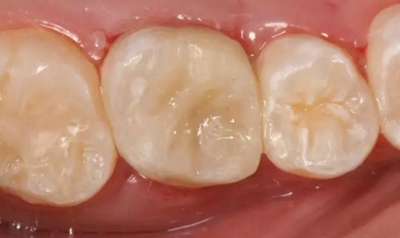

病例一 女性,20歲,大學生,要求補牙,檢查口內(nèi)可見A6大面積缺損,近中牙齦息肉,拍X片,根管充填物略差,但根周未見明顯陰影,口內(nèi)檢查無叩痛。建議患者冠延長手術+高嵌體修復。

患牙遠中邊緣嵴完整,強度沒有降低,故擬保留遠中邊緣嵴,高嵌體修復。首先去除腐質(zhì)及原墊底材料,流體樹脂+3M Z350XT樹脂墊底。局麻下行冠延長手術。在此需要提及個人的一個觀點。冠延長手術原則上要求3-6個月以上才能永久修復。但是個人喜歡后牙肩臺建立在齦上,所以修復后的修復體邊緣位于牙齦上方1mm,對牙周的愈合影響較?。ㄈ绻麨辇l下邊緣則要慎重),故該患者術中按照齦上邊緣的設計進行冠延長手術。以下為術中: